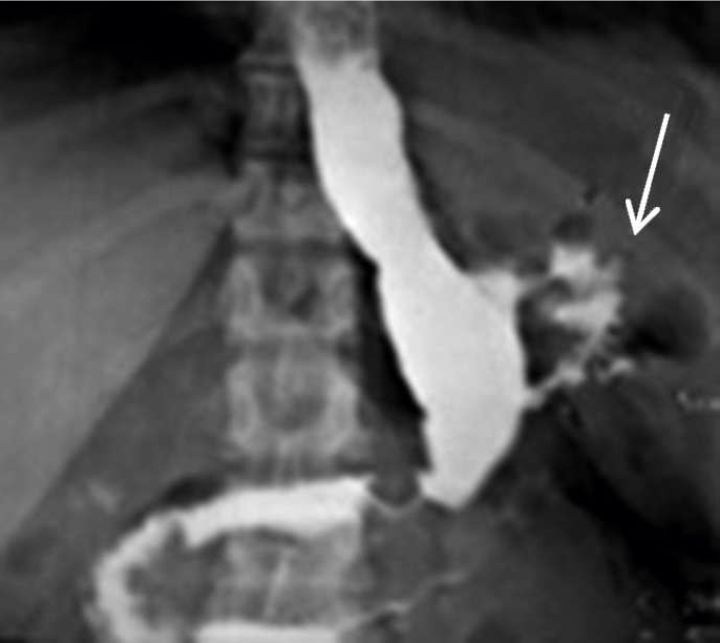

Figura 5

EGD de control en proyección AP

donde se observa el trayecto de una fístula enterocutánea (flechas). (Paciente Nº3)

La principal utilidad del estudio de EGD post-operatorio es el seguimiento evolutivo de las fugas drenadas hasta su cierre. Figuras 4,5 y 6.